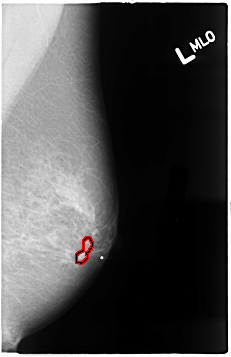

B_3038_1.LEFT_MLO

LEFT_MLO LINES 4640 PIXELS_PER_LINE 2992 BITS_PER_PIXEL 12 RESOLUTION 50 OVERLAY

FILE: B_3038_1.LEFT_MLO.OVERLAY

TOTAL_ABNORMALITIES 1

ABNORMALITY 1

LESION_TYPE MASS SHAPE LOBULATED MARGINS CIRCUMSCRIBED

ASSESSMENT 4

SUBTLETY 3

PATHOLOGY MALIGNANT

TOTAL_OUTLINES 1

BOUNDARY